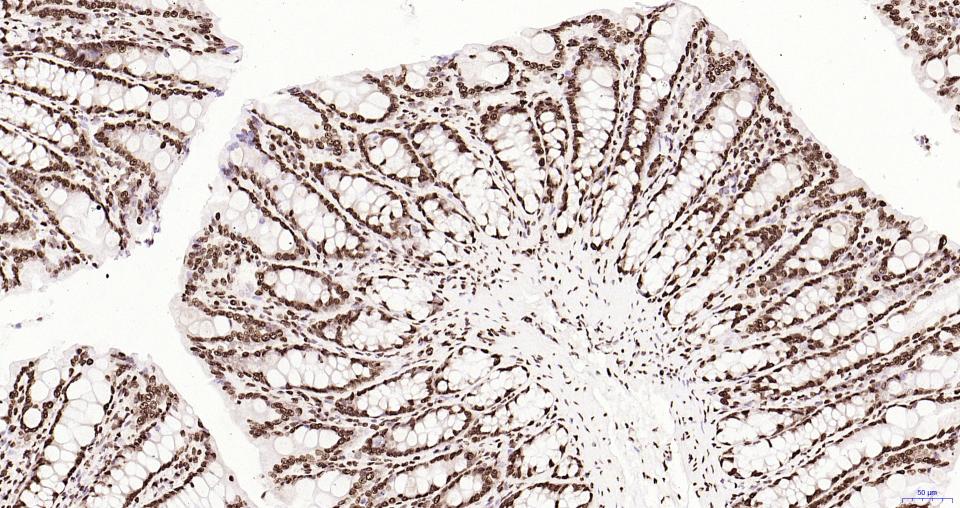

Paraformaldehyde-fixed, paraffin embedded Mouse Stomach; Antigen retrieval by boiling in sodium citrate buffer (pH6.0) for 15 min; Antibody incubation with Histone H2A.X Monoclonal Antibody, Unconjugated(bsm-61080R) at 1:200 overnight at 4°C, followed by

Paraformaldehyde-fixed, paraffin embedded Rat Stomach; Antigen retrieval by boiling in sodium citrate buffer (pH6.0) for 15 min; Antibody incubation with Histone H2A.X Monoclonal Antibody, Unconjugated(bsm-61080R) at 1:200 overnight at 4°C, followed by co

Paraformaldehyde-fixed, paraffin embedded Mouse Colon; Antigen retrieval by boiling in sodium citrate buffer (pH6.0) for 15 min; Antibody incubation with Histone H2A.X Monoclonal Antibody, Unconjugated(bsm-61080R) at 1:200 overnight at 4°C, followed by co

Paraformaldehyde-fixed, paraffin embedded Rat Colon; Antigen retrieval by boiling in sodium citrate buffer (pH6.0) for 15 min; Antibody incubation with Histone H2A.X Monoclonal Antibody, Unconjugated(bsm-61080R) at 1:200 overnight at 4°C, followed by conj